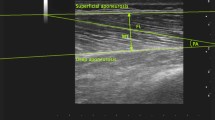

All ultrasound images were acquired by an expert operator (MVF) with the same ultrasound device throughout the whole study (Aixplorer Ultimate, SuperSonic Imagine, Aix-en-Provence, France) using a linear 50 mm transducer (SuperLinear SL18-5, SuperSonic Imagine, Aix-en-Provence, France). Participants were asked to lie prone on a massage bed and were instructed to rest with extended knee joints, and to relax completely during image acquisition with their feet placed just outside the bed frame in order to avoid any lower limb imbalances. Five minutes of rest in this position were provided for body fluid shift stabilization.

For the panoramic ultrasound scans, the region of interest (ROI) was determined and marked as follows. Firstly, a mark was drawn at 50% of the distance between the greater trochanter and the mid patella point. In second instance, other marks were drawn with a permanent ink pen at the 30%, 40% and 60% of the femur length (distal to proximal, thus 0% was representing the mid patellar point and 100% the great trochanter). The ROIs were identified laterally, from the borders of vastus lateralis muscle, and medially, until the borders of the gracilis muscle, similar to the guidelines suggested by Balius and colleagues25. Multiple ROIs were identified in a similar fashion to the study of Kositsky and colleagues26, the reason being that distinct muscles present their CSA peak value at distinct muscle sites. In addition, obtaining CSA values at multiple sites allowed us to reconstruct a bigger portion of muscle volume of the hamstrings muscle group.

At each ROI, the transducer was placed on the lateral portion of the posterior thigh (just before the Biceps femoris long and short heads muscle borders) and then moved on the transversal plane in a lateral-to-medial fashion until the end of borders of the semimembranosus and the start of gracilis muscle were identified, then the panoramic acquisition was stopped. We have carefully ensured that the images were collected at the right angle in the transverse plane by using a plastic guide placed on the skin of the volunteer’s thigh, similar to the one used by Noorkoiv et colleagues13. The transducer was kept in contact with the guide throughout the whole acquisition of CSAs, thus we ensured that the right CSA path was followed while keeping the transducer perpendicular to the skin. The operator took meticulous care in keeping the pressure as constant as possible during the entire image acquisition. For all scans, transmission gel was used to improve the acoustic contact and to keep the pressure on the skin to a minimum. For the purpose of test–retest reliability assessment as outlined below, EFOV scans were acquired twice after completely removing the transducer from the skin and with 5 min rest period in between.